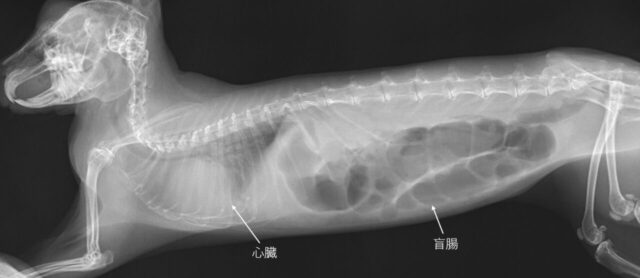

検査の結果、心嚢水のため大きくふくれていた心臓が小さくなり肺に溜まった胸水もなくなっているとのこと

今後は呼吸の様子を見ながら酸素室から出て運動する時間を増やして足腰が弱らないようにすること、月1回の往診で変化が起きないかをみていくことになりました。

ポッキーは順調に回復し、チモシーも野菜もペレットもよく食べ、うんちも立派なものをたくさん出してくれるようになりました。7月末の1日の大半を酸素室の外で生活できるようになりました

院長先生からも「今後は薬も酸素室も不要」とお墨付きをいただき病気する前と変わらず生活ができるようになりました